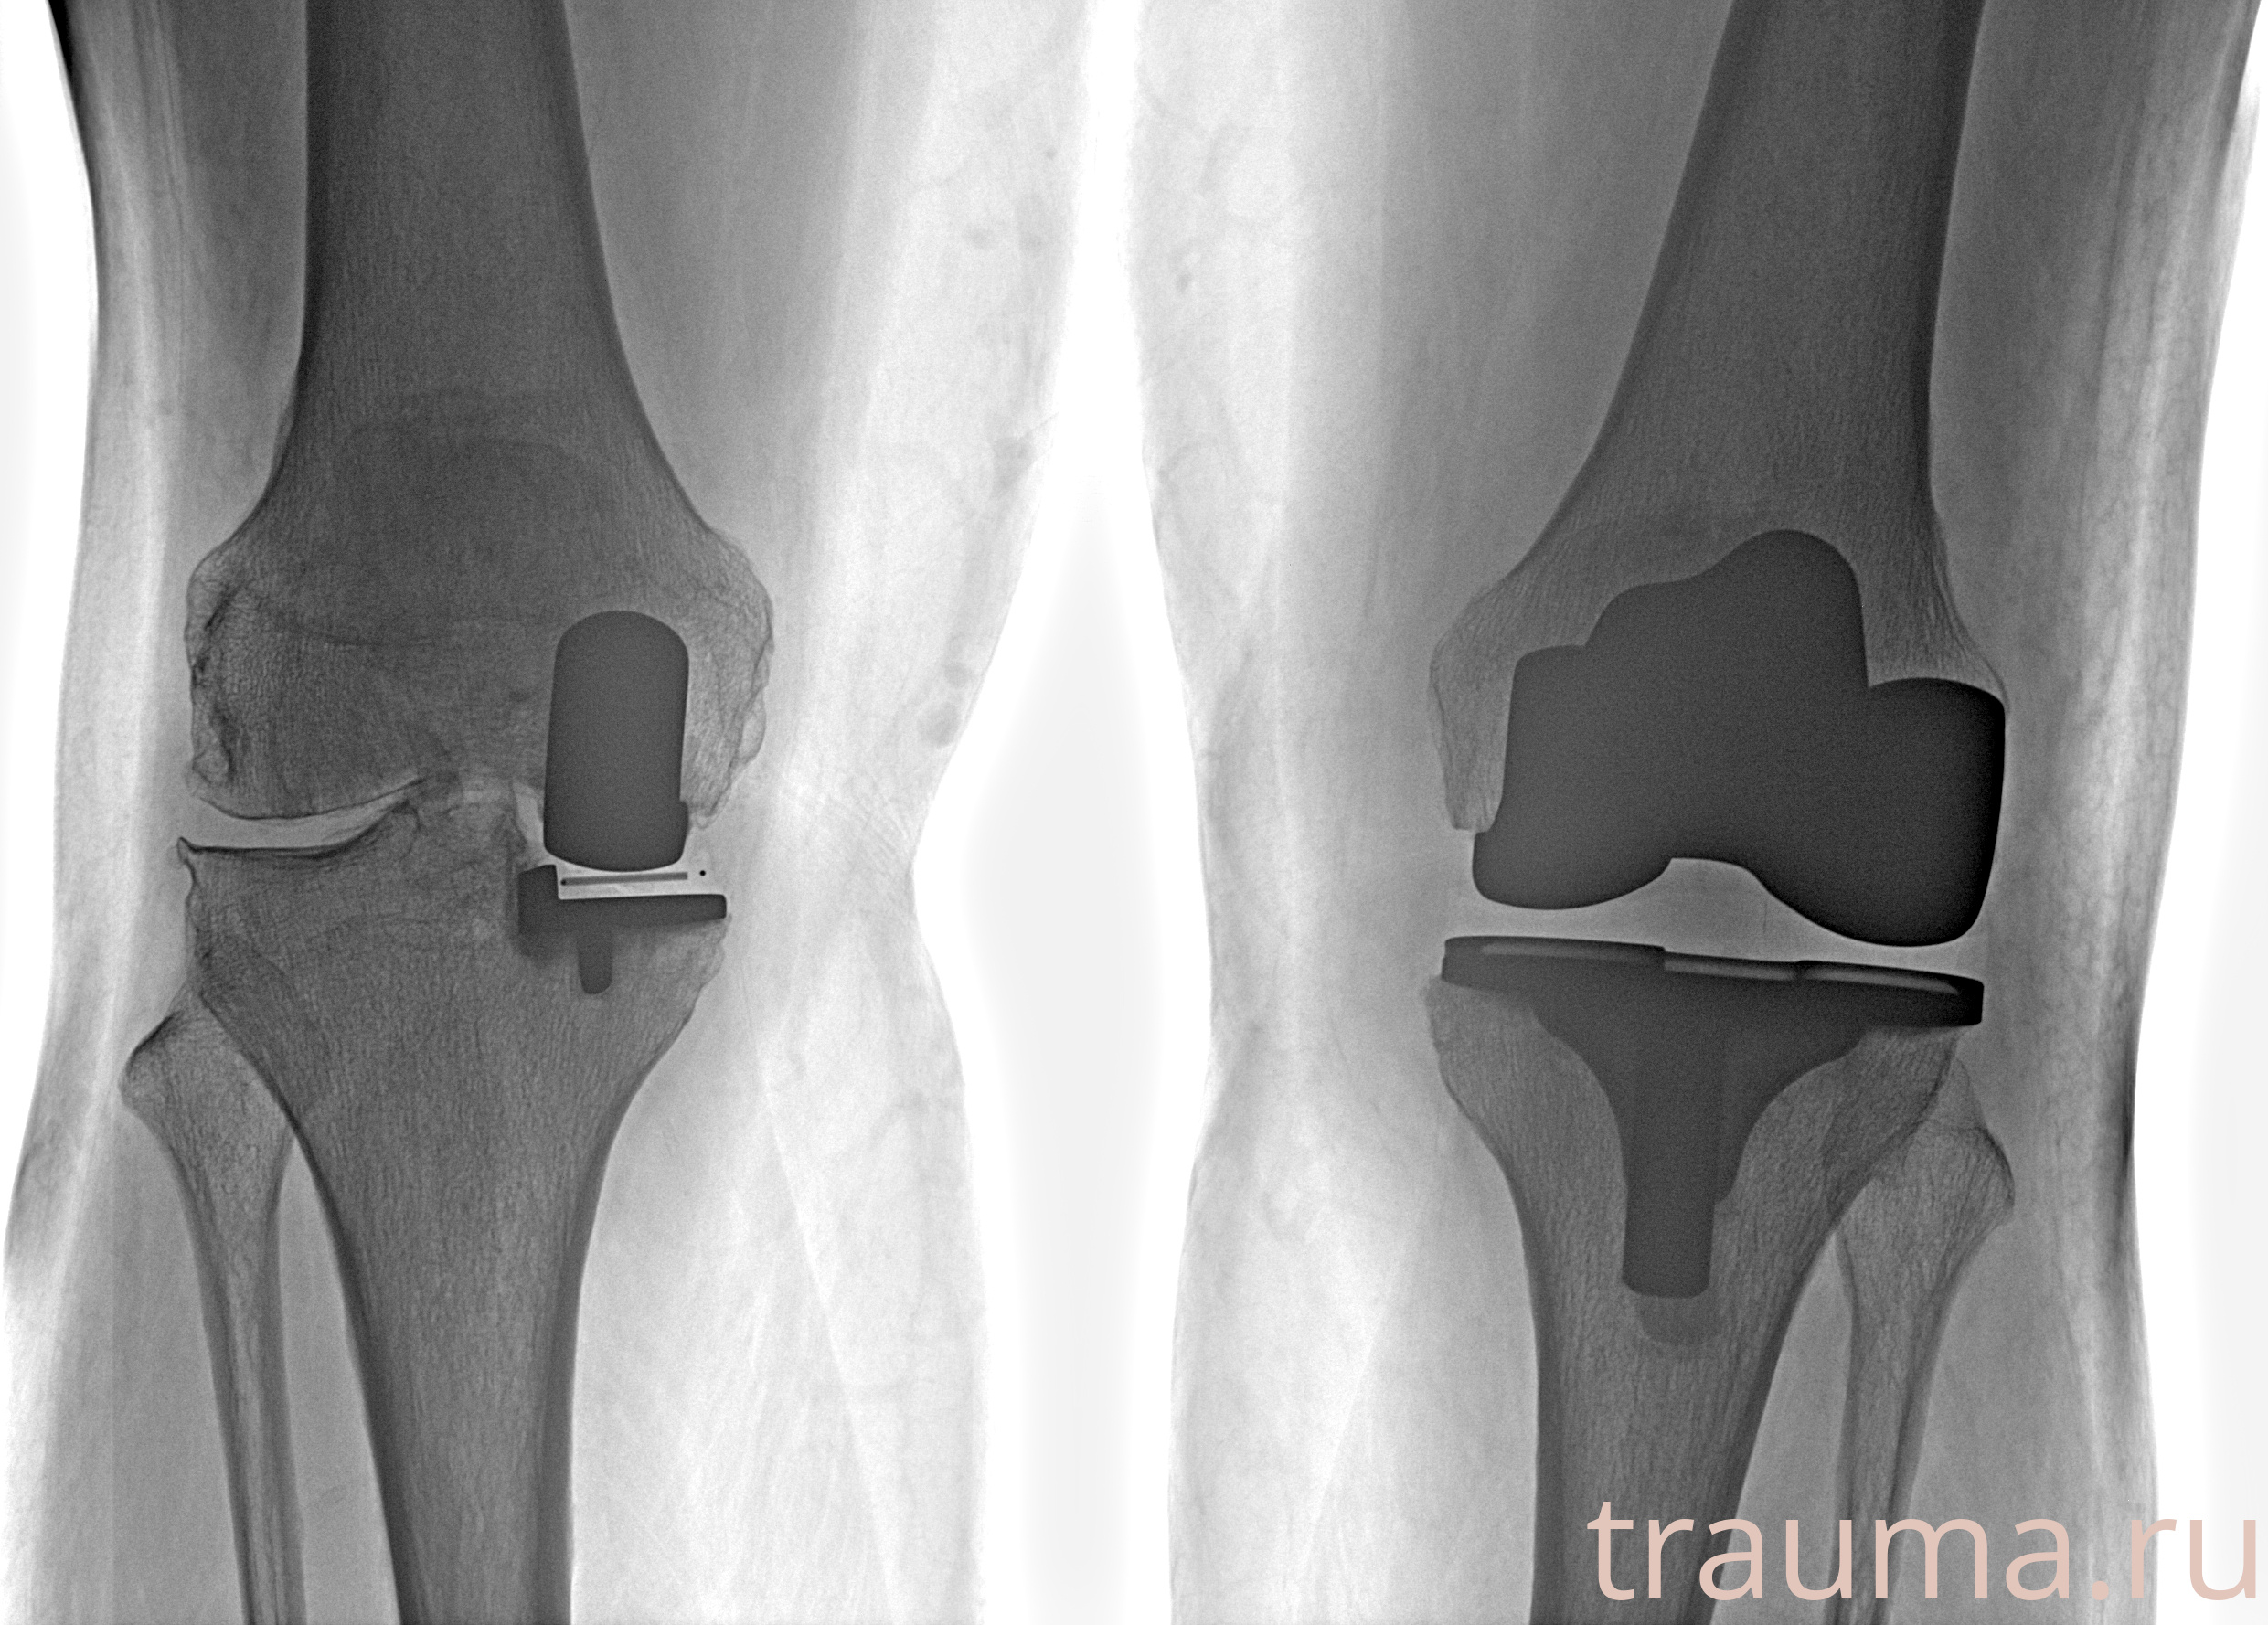

Правый

Рентгенограммы